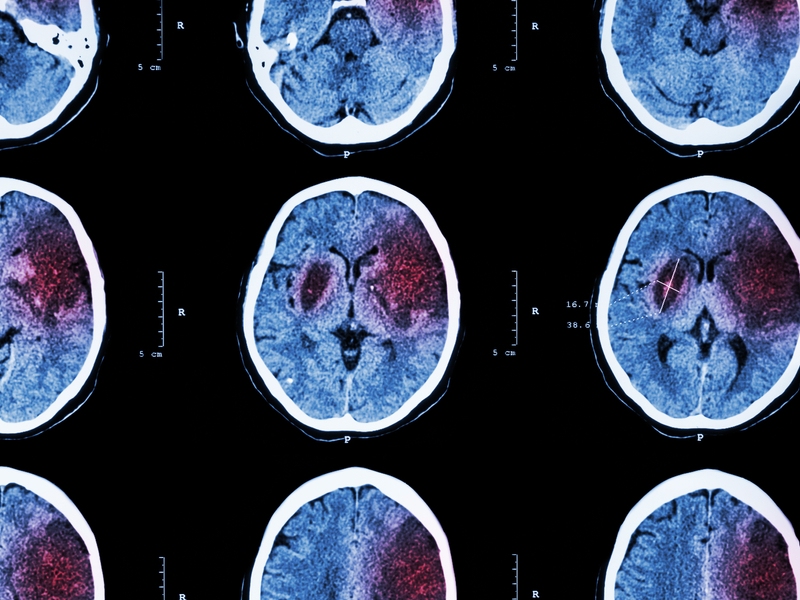

Doctors diagnose strokes in the emergency room by asking about your medical history, checking your brain and nerve function with a physical exam and doing imaging tests. Since quick treatment is key to preventing serious damage, doctors work fast to confirm a stroke and start care right away. Your ER doctor might order a computerized tomography (CT) scan of your brain to check for a stroke. However, if it's an ischemic stroke caused by a blocked blood vessel, it might not show up right away because early changes in the brain can be too subtle for the scan to detect. Still, the scan helps doctors quickly decide on the best emergency treatment.

• Imaging tests

Your provider will order tests to view blood flow within your brain and see whether you are having a stroke, as well as its type and location. This helps them determine the correct course of treatment.

• Computerized tomography (CT) scan: A CT scan provides immediate information about the type, location and size of a stroke.

• CT angiogram: An angiogram, or angiography, shows blood flow in your brain and reveals any bleeds or blockages.

• Magnetic resonance imaging (MRI) scan: MRI uses magnets and radio waves to create a detailed image of the arteries, veins and soft tissues in your brain. This image can characterize the size and location of a stroke, even if the stroke is very small.